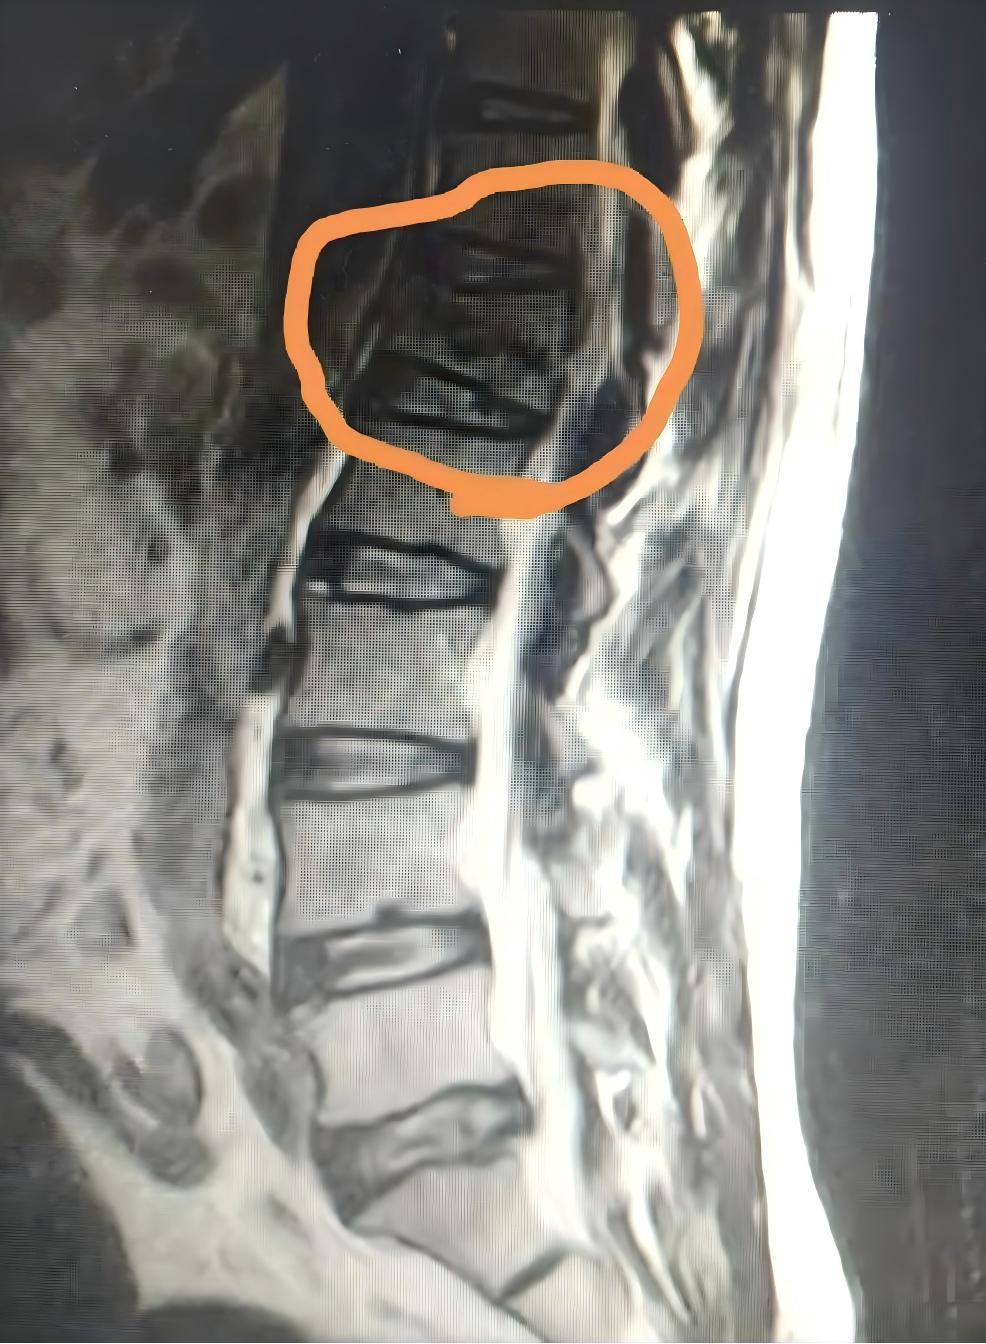

The patient, an elderly female with a history of recurrent lumbar sprains, experienced acute onset of symptoms when forcefully pulling a heavy object, with no history of trauma. The Floating Needle therapy yielded unsatisfactory results. Drawing a parallel with Case 1, the decision was made to have the patient undergo imaging at the hospital. In the afternoon, the patient returned with the lumbar MRI report, which revealed compression fractures of the L1 and L3 vertebrae.